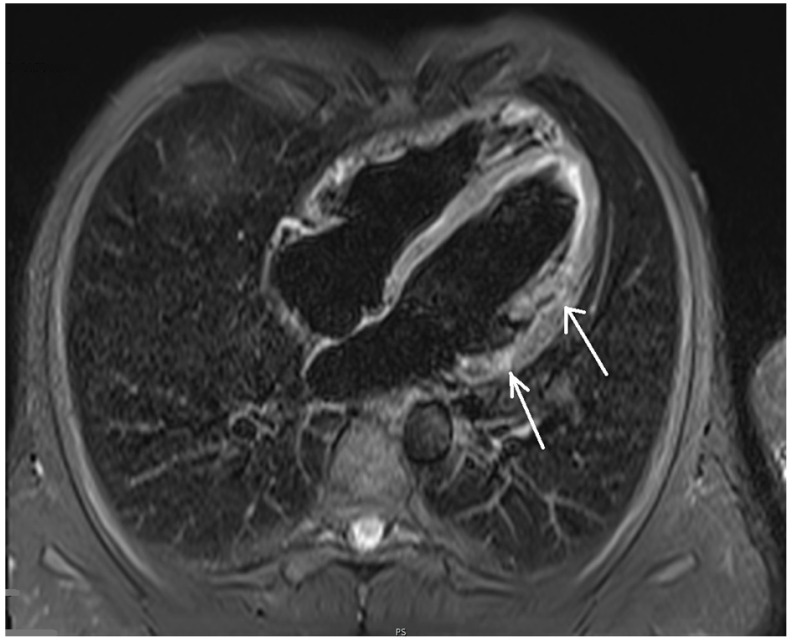

In the cardiovascular magnetic resonance imaging of the heart, left and right ventricle sizes were within normal ranges, correct wall thickness, correct global and segmental contractility and normal ejection fractions of both ventricles (58% and 51%, respectively) were observed. After administration of the contrast agent, the areas of delayed epicardial and intramuscular enhancement were visualized, mainly in the area of the inferior and lateral walls of the left ventricle. No signs of myocardial edema and hyperemia, met in acute myocarditis, could be visualized (Figure 5). Those fibrotic lesions formed the picture of nonischemic myocardial damage in the picture of past myocarditis [ref. 11,ref. 12,ref. 13].